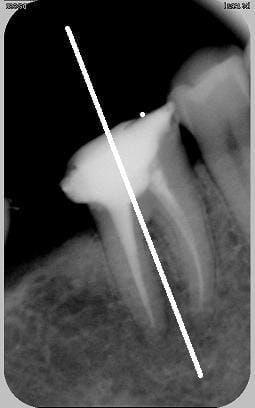

Oui, juste qu'il me semble que les dents du secteur molaire/prémolaires devraient être prises avec une radio orientée avec son granbd axe horizontalement...et pas l'inverse comme pour les Incisives et Canines. Bon, je chipote, je te l'accorde. Tant qu'on voit ce que l'on veut finalement... ;-)

PS : En fait, en faisant comme tu fait, tu es obligé de reculer ton capteur par rapport à ta dent (surtout pour les dents sup)...et plus tu t'éloignes, moins ta radio est bonne et précise car la moindre angulation a d'autant plus d'incidence sur les déformations. Je ne sais pas si je suis assez clair. Oui, non ?

je crois...cet axe là?

Je pense, amigo athos!!! (histoire de trouver qquchose :-))))

Quand je parlais de grand axe de la radio, c'est la longueur du capteur qu'il fallait comprendre, pas celui de la dent radiographiée. En gros, pour des molaires/prémolaires, ta radio doit être regardée comme un écran 16/9. Pour les I et C, comme le portarit de la Joconde.

capteur "couché" alors?

dis donc t'es sur que ça va diminuer les déformations ça? enfin bon, je ferai comme ça desormais, mais si je ne vois pas une amélioration merveilleuse de l'image je serai tout déçu déçu déçu...

oui, mais aussi je ne suis pas persuadé que dans le cas ou on veut faire une correction parallectique (heu...pas sûr de l'orthographe du terme, mais = cale, faisceau déporté et deformations proportionnelles) raccourcir la longueur du capteur ne complique pas la chose

ps: je t'ai dit que je tenais le capteur avec mes doigts (ééhhhh oui...je sais) plaqué contre la dent, plus près et plus parrallele on peut pas, le generateur est a anode déportée, je n'utilise pas de viseur mais je m'applique a ce que le faisceau soit bien perpendiculaire au plan et centré sur le milieu de....l'objet ou le capteur? hmmm?...